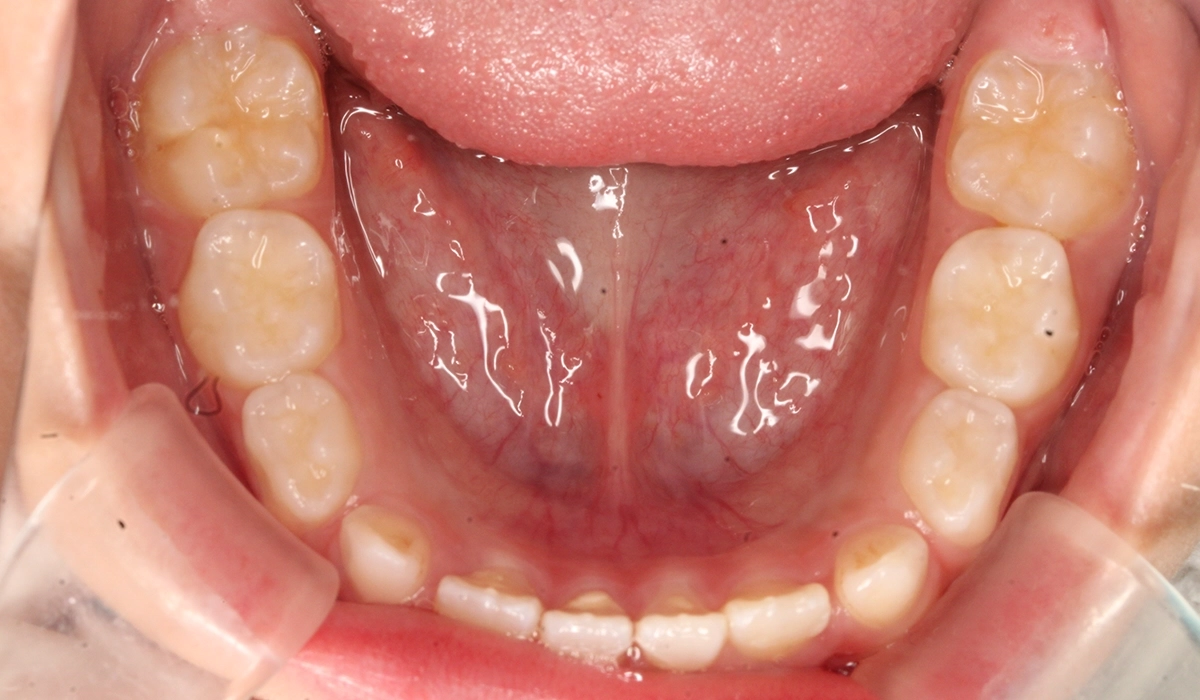

術前:上顎

術後:上顎